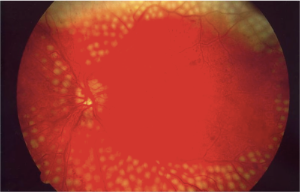

Laser is a highly focused and concentrated beam of light that is usually performed to decrease leakage in the retina, treat abnormal blood vessel growth, or create a beneficial scarring effect that can help prevent a retinal detachment.